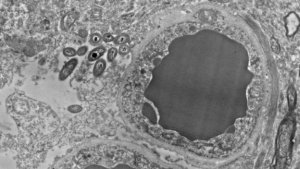

La docteure Rosalinda Roberts, accompagnée de son équipe du Psychiatry and Behavioral Neurobiology de l’Université de l’Alabama, sont à l’origine de cette découverte. Ils ont en effet étudié le cerveau de 34 personnes ; la moitié étaient des sujets sains et l’autre moitié souffrait de schizophrénie. De plus, une étude parallèle sur des souris a été réalisée pour exclure l’hypothèse selon laquelle la bactérie ne serait apparue que post-mortem. Mais aussi pour éviter qu’il puisse y avoir une quelconque erreur due à une contamination.

Les chercheurs ont donc pu observer la présence de bactéries dans le cerveau humain et chez les souris. Et ce non seulement dans des situations non infectieuses ou traumatiques, mais aussi au niveau de plusieurs régions du cerveau. Principalement dans la substance noire, l’hippocampe et le cortex préfrontal, et très peu dans le striate. De plus, aucun des cerveaux examinés ne présentait d’inflammation.

Image principale de Rosalía Roberts, Courtney Walker et Charlene Farmer